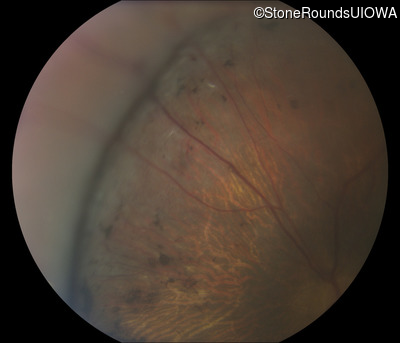

Fundus Photography - Left - 10/100 -2

Exemplar